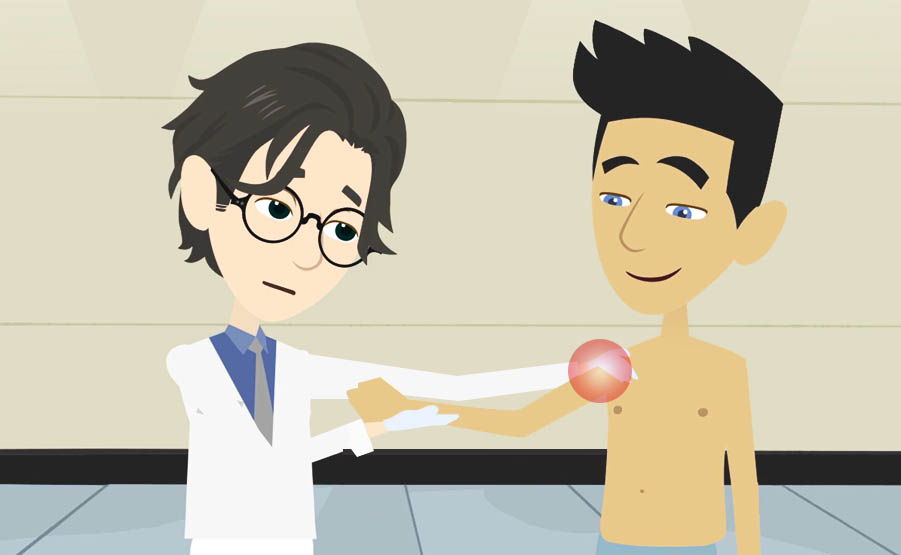

Un fisioterapista utilizza una varietà di tecniche per aiutare i pazienti a raggiungere il loro pieno potenziale di movimento, ridurre il dolore e migliorare la funzione fisica.

- Utilizzare tecniche manuali: un fisioterapista può utilizzare tecniche manuali, come la manipolazione articolare, per aiutare a ridurre il dolore e migliorare la funzione.